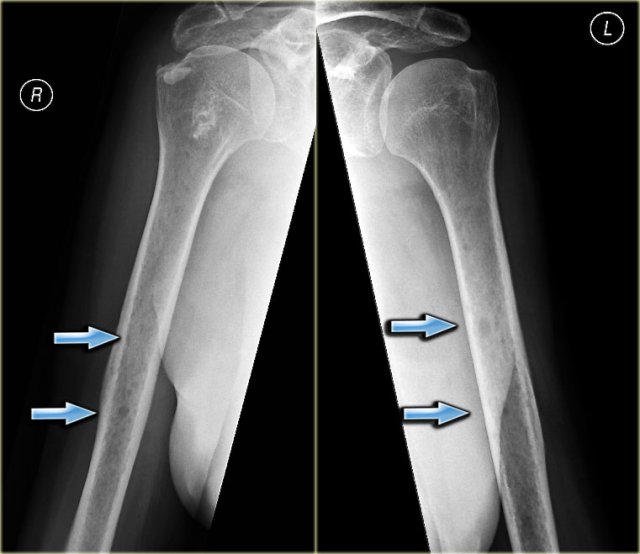

Melorrheostosis Melorrheostosis

Melorrheostosis of proximal humerus.